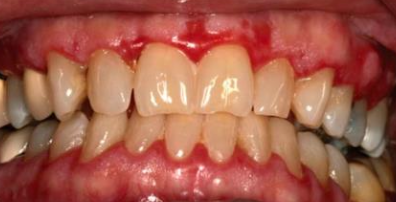

• 慢性,很少自限性 (會越來越嚴重)

• 口內堅固 vesicles/ bullae,α6 型只有口內病灶

• 皮膚結疤,但口內不會 → 無小口症

• 脫屑性牙齦炎(desquamative gingivitis)

• 眼球沾黏